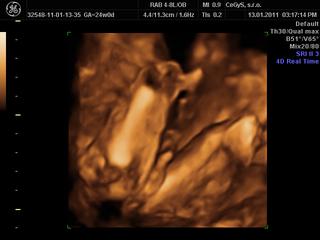

Babule tak sme doma z 3D/4D, mame uzasny zazitok, maly je krasny, podoba sa na naseho Vilka, bradicku, nostek, pusinku maju uplne rovnaku) Dr.bol perfektny, super nam povysvetloval, pokecali sme, venoval sa nam asi hodinku, porobil nam asi 20 fotiek a videii a aj nam vytlacil 1 fotecku, pohral sa s tym, aj nam maleho pomeral, nahodil do tabuliek, proste vsetko mame skoro 800 g a sme tyzden popredu podla malickeho, je to fakz super, mozte sa tesit, mne sa bude dnes o tom urcite snivat) 😵

Pridam vam aj fotecku) 😉